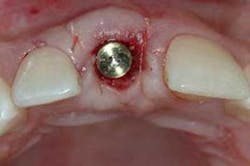

Of all the problems that can occur with implant placement in the anterior, not controlling the zenith of gingival contour may be the most troublesome when it comes to anterior esthetics. Gingival zenith or height of gingival contour is defined as the apex of the gingival height. There are many ways to lose several millimeters of peri-implant mucosa, and it has been shown that even a 1 mm apical displacement of peri-implant mucosa may result in insurmountable limitations in anterior implant esthetics. Things such as deep implant placement, buccal resorption, and relative tooth eruption are just some of the things that can cause this loss of tissue.

When planning surgery with my periodontist, we both decide where we want the zenith to be esthetically, and then plan implant placement 3 mm apical and 2 mm palatal to this location. Biologically speaking, this location will allow us to preserve the zenith from a placement standpoint. Keep in mind that we need to have the tissue healthy and under control prior to starting any procedure.

Now comes the tricky part — the provisional. Prosthetic control of peri-implant tissue is achieved by properly utilizing your abutment and provisional form. When placing the provisional, it is important to maintain gingival zenith. When fabricating a provisional, my rule of thumb is to create a flat or slightly convex surface facially and lingually, and a concave surface interproximally. This will minimize impingement on the tissue interproximally and, if anything, allow for “overgrown tissue” to develop. This tissue can be easily contoured prior to final placement to give an ideal esthetic gingival architecture.